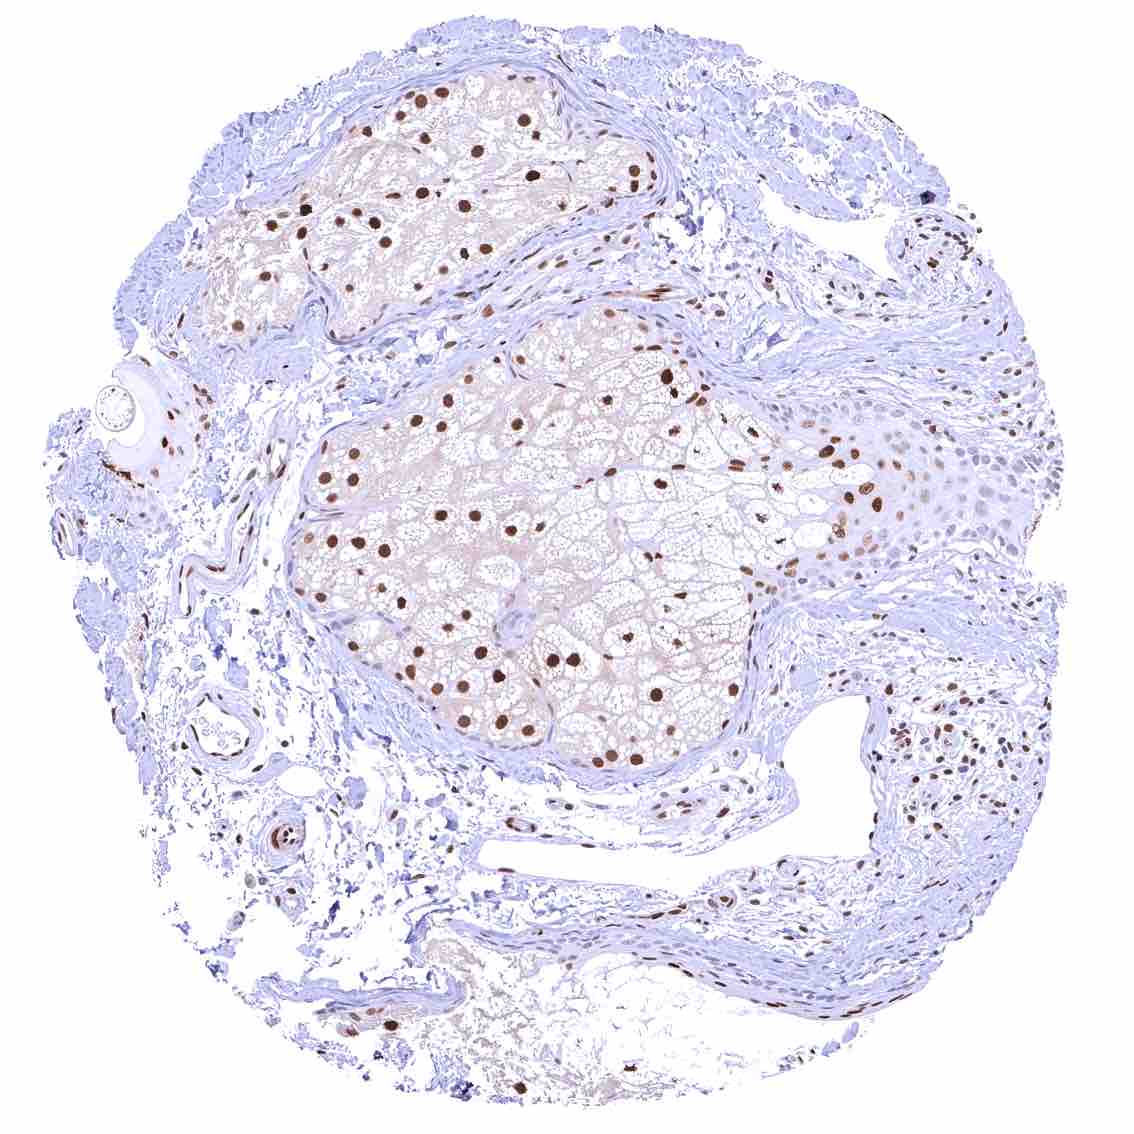

Skin – Moderate to strong nuclear p27 staining occurs in a large fraction of squamous epithelial cells and predominates in the more mature cell layers (top 50_ of the epidermis).

Skin, hairfollicel and sebaceous glands – Moderate to strong nuclear p27 staining in all cells of sebaceous glands. .jpeg